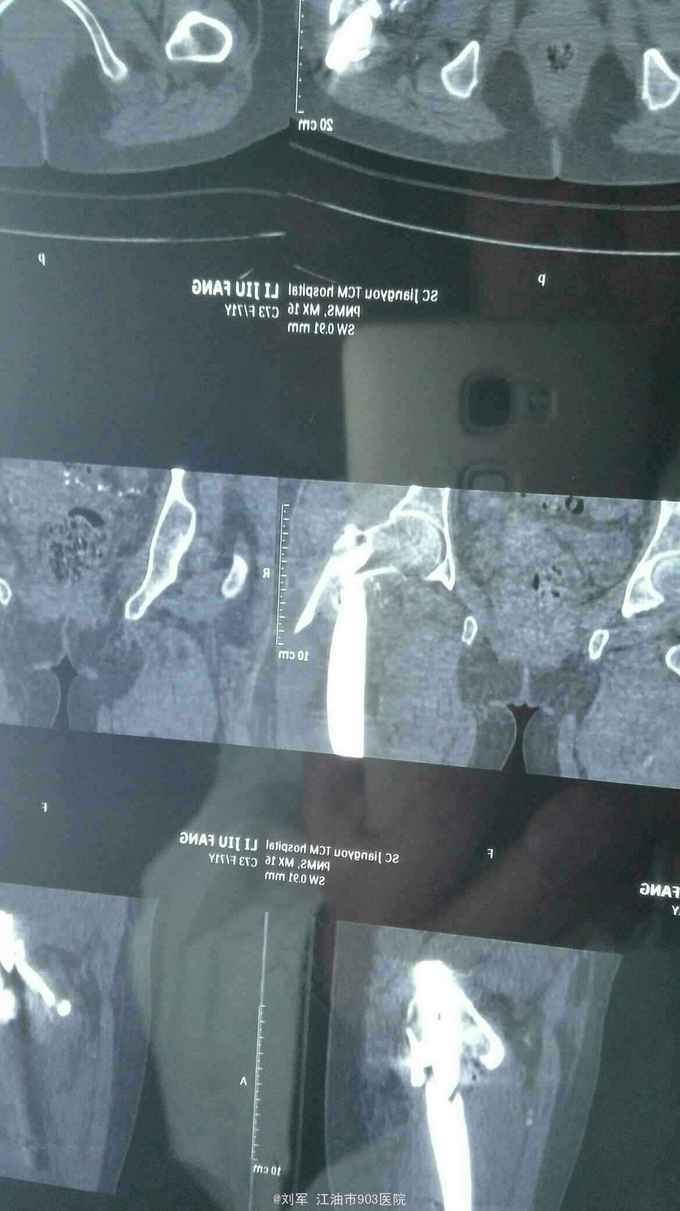

左侧股骨粗隆骨折术后骨折再移位20天。 患者74岁女性,20天前于外院行左股骨粗隆骨折PFNA内固定术。术后复查X片提示骨折再移位,内固定失败。来我院就诊。既往有糖尿病病史。入院时血糖控制可。贫血,低蛋白明显。HGB:68g/L。

左髋部肿胀,切口干燥,未拆线,无明显红肿、渗液。左髋关节活动障碍。

左股骨粗隆骨折术后再移位,2型糖尿病,